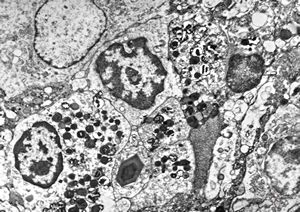

M,61y. | spleen - hemangioma v.s. … erythrophagocytosis